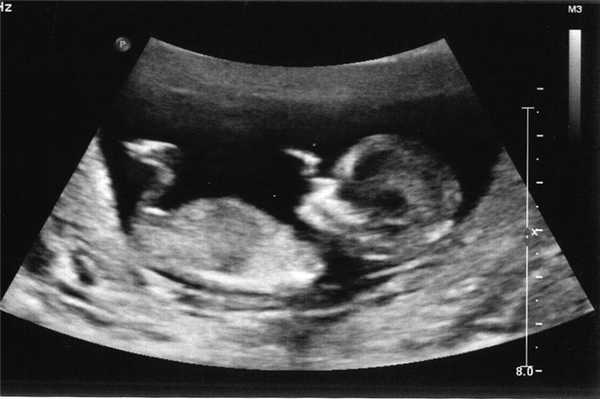

Ультразвуковое исследование на 31-32 неделе

Это время проведения третьего скрининга беременных. Ребенку становится еще теснее в животе матери, в связи с чем на экране УЗИ врач может видеть только часть его тела. В это время малыш должен перевернуться головкой вниз и занять положение, удобное для предстоящих родов. Это происходит за счет относительно большого размера головы малыша в сравнении с остальным телом.

Скрининг проводится для оценки течения беременности и выбора тактики ведения родов. Гинеколог может порекомендовать кесарево сечение, если во время скрининга выявлены такие состояния:

- неправильное положение ребенка;

- преждевременное старение плаценты;

- нарушение плацентарного кровотока;

- многоводие или маловодие;

- обвитие пуповиной;

- слишком большой вес малыша.

При возникновении любых подозрений, пациентку направляют на прохождение генетического анализа.